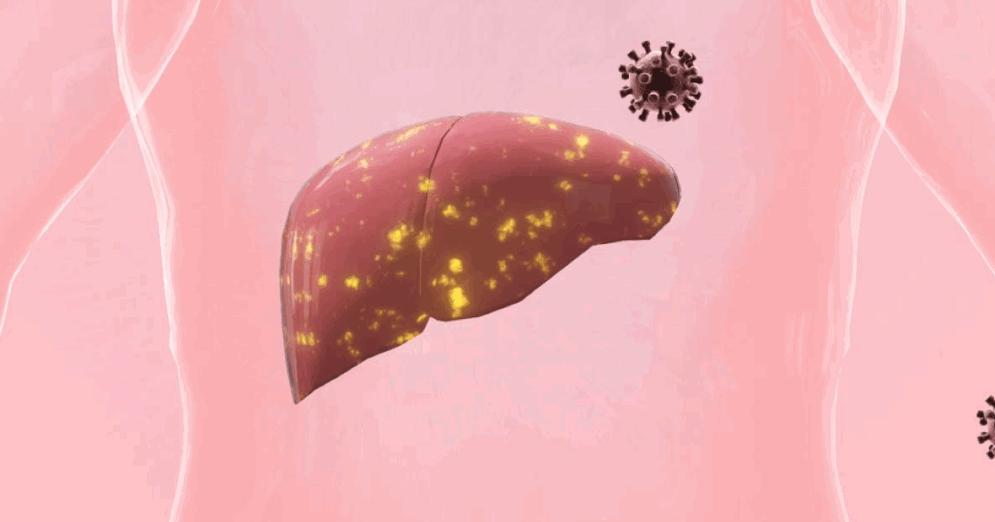

肝臟彩超,提示肝纖維化、肝硬化

肝癌發展存在典型的“三步曲”,即肝炎—肝硬化—肝癌。約70%的原發性肝癌發生在肝硬化基礎上,在我國約40%肝硬化合並肝癌。

肝功能受損較重時,可出現以下異常:

• 血清報告,如白蛋白水平明顯下降,轉氨酶和膽紅素水平明顯超標,甲胎蛋白AFP明顯高於正常;

• 超聲報告,通常可見肝臟表面凹凸不平、體積異常、肝實質內回聲不勻增強、纖維化等字眼。

• 每年一次常規體檢:肝硬化目前尚無特效療法,關鍵在於儘早診斷,針對病因和症狀進行干預。

• 控制肝臟炎症:如脂肪肝。脂肪肝早中期是可逆的,建議均衡營養,控制減重,但別減肥太快。

• 限制飲酒:酒精主要靠肝臟代謝,最好滴酒不沾。不濫用保健品,不喫發黴食物。